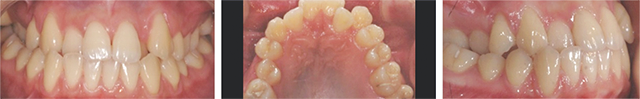

공간부족으로 인하여 치아가 제대로 나오는 못한 2급 부정교합 환자입니다. 고운미소에서 악궁을 넓혀주는 급속구개확장술 (RPE)를 적용하여 비발치 교정을 진행하였습니다.

급속구개확장술 (RPE) 장치로 빠르게 상악이 확장되었습니다. 넓어진 공간으로 치아가 이동이 되어 발치를 하지 않고 가지런하게 치아교정이 되었습니다.